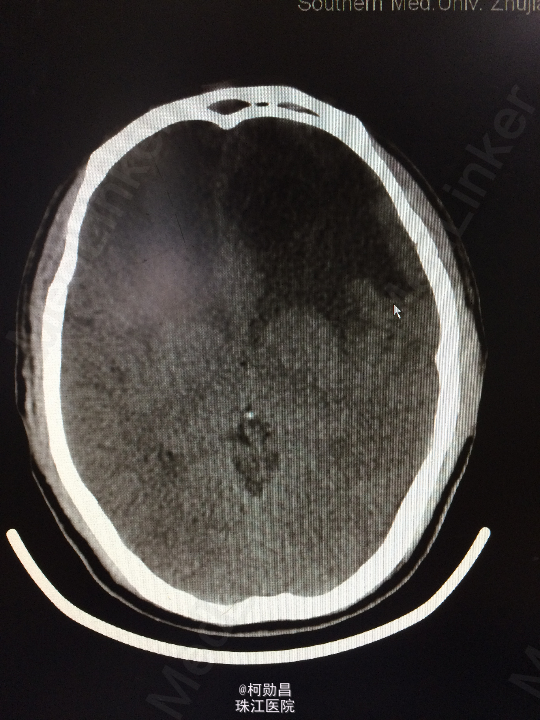

主诉:头痛伴左眼视力下降半年 病史:患者46岁男性,缘于半年前无明显诱因出现头痛,当时未予特殊处理,后症状进行性加重,并发左眼视力下降,于当地医院行头颅CT及MR检查提示颅内占位,为进一步治疗而入我院。 既往病史:5年前曾患鼻咽癌

查体:神志清楚,对答流利,左侧眼裂变小,左侧瞳孔散大,直径4mm,对光反射迟钝,左眼视力下降。右侧正常。 辅助检查:头颅MR提示前颅底筛沟通病变

诊断:鼻咽癌脑转移 处理:全麻下行颅筛沟通占位切除术,术后病理提示:鼻咽非角化鼻咽癌脑转移